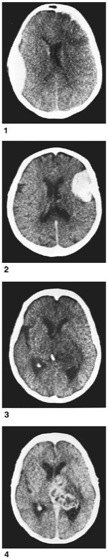

Computertomographische Aufnahmen zu verschiedenen Läsionen des Gehirns. Das Hirngewebe ist deutlich vom umgebenden Schädelknochen zu unterscheiden, dunkle Gebiete in der Hirnmitte stellen die Ventrikel (Hirnkammern) dar. 1 Bluterguß am linken Rand des Gehirns und Verkleinerung der Ventrikel durch Schwellung der beiden Hirnhälften; 2 Meningiom (gutartige Geschwulst) am rechten Rand des Gehirns, mit iodhaltigem Kontrastmittel deutlich sichtbar; 3 bösartiger Tumor in der Hirnmitte, der durch Verdrängung der Ventrikel auffällt (Epiphyse nahe der Hirnmitte als heller, bohnenförmiger Fleck zu erkennen); 4 derselbe Tumor wie in 3, durch Kontrastmittel sichtbar gemacht.